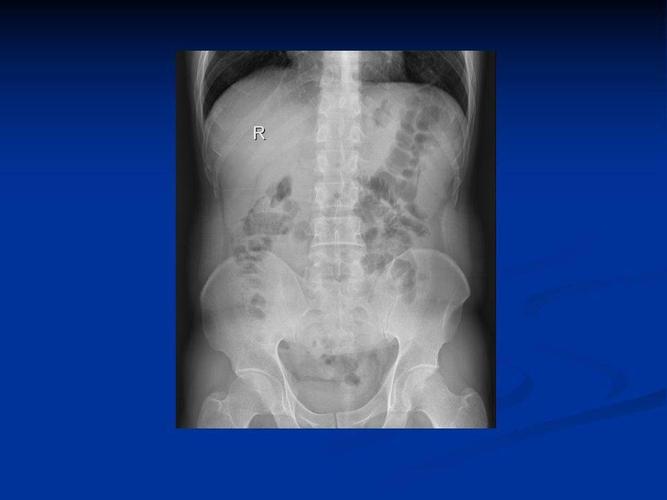

肠梗阻图片

肠梗阻图片,肠梗阻卡通

高清图片文字讲解肠梗阻的分类及影像学表现

肠梗阻

肠梗阻气液平面图片

腹部平片肠梗阻图片

低位肠梗阻图片

高位性肠梗阻图片

肠梗阻片子

肠梗阻影像学图片

肠梗阻片子图片